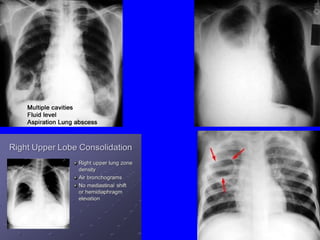

Air-fluid level in Lung Abscess. Note small free PE in RAir-fluid level in Lung Abscess. Note small free PE in R

60 Air-fluid level inLung Abscess. Note small free PE in RAir-fluid level in Lung Abscess. Note small free PE in R pleural cavitypleural cavity

Complications of pneumoniaComplicationsof pneumonia IntrathoracicIntrathoracic • P. effusion, empyemaP. effusion, empyema • Collapse, consolidationCollapse, consolidation • L. abscess, pneumatoceleL. abscess, pneumatocele • PneumothoraxPneumothorax ExtrathoracicExtrathoracic • Septicemia, meningitisSepticemia, meningitis • Dehydration, myocarditisDehydration, myocarditis • Pericarditis, acidosis, dyselectrolytemiasPericarditis, acidosis, dyselectrolytemias